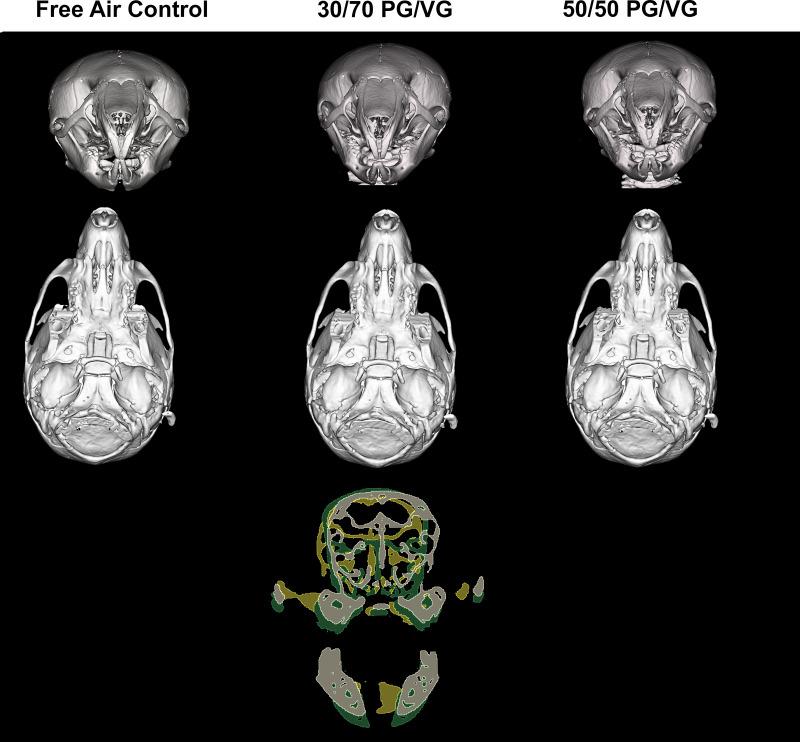

In utero exposure to electronic cigarette carriers alters craniofacial morphology.

Adult breeder mice were utilized to generate in utero ENDS component exposed litters including free air exposure (control), 30/70 PG/VG, and 50/50 PG/VG groups. The resulting pups were assessed at postnatal day 14 for skull morphology.

Data demonstrate significant reductions in body weight, facial, and cranial dimensions, where there was a significant reduction in growth for the 30/70 PG/VG exposed group. There were no significant differences found between control and 50/50 PG/VG.